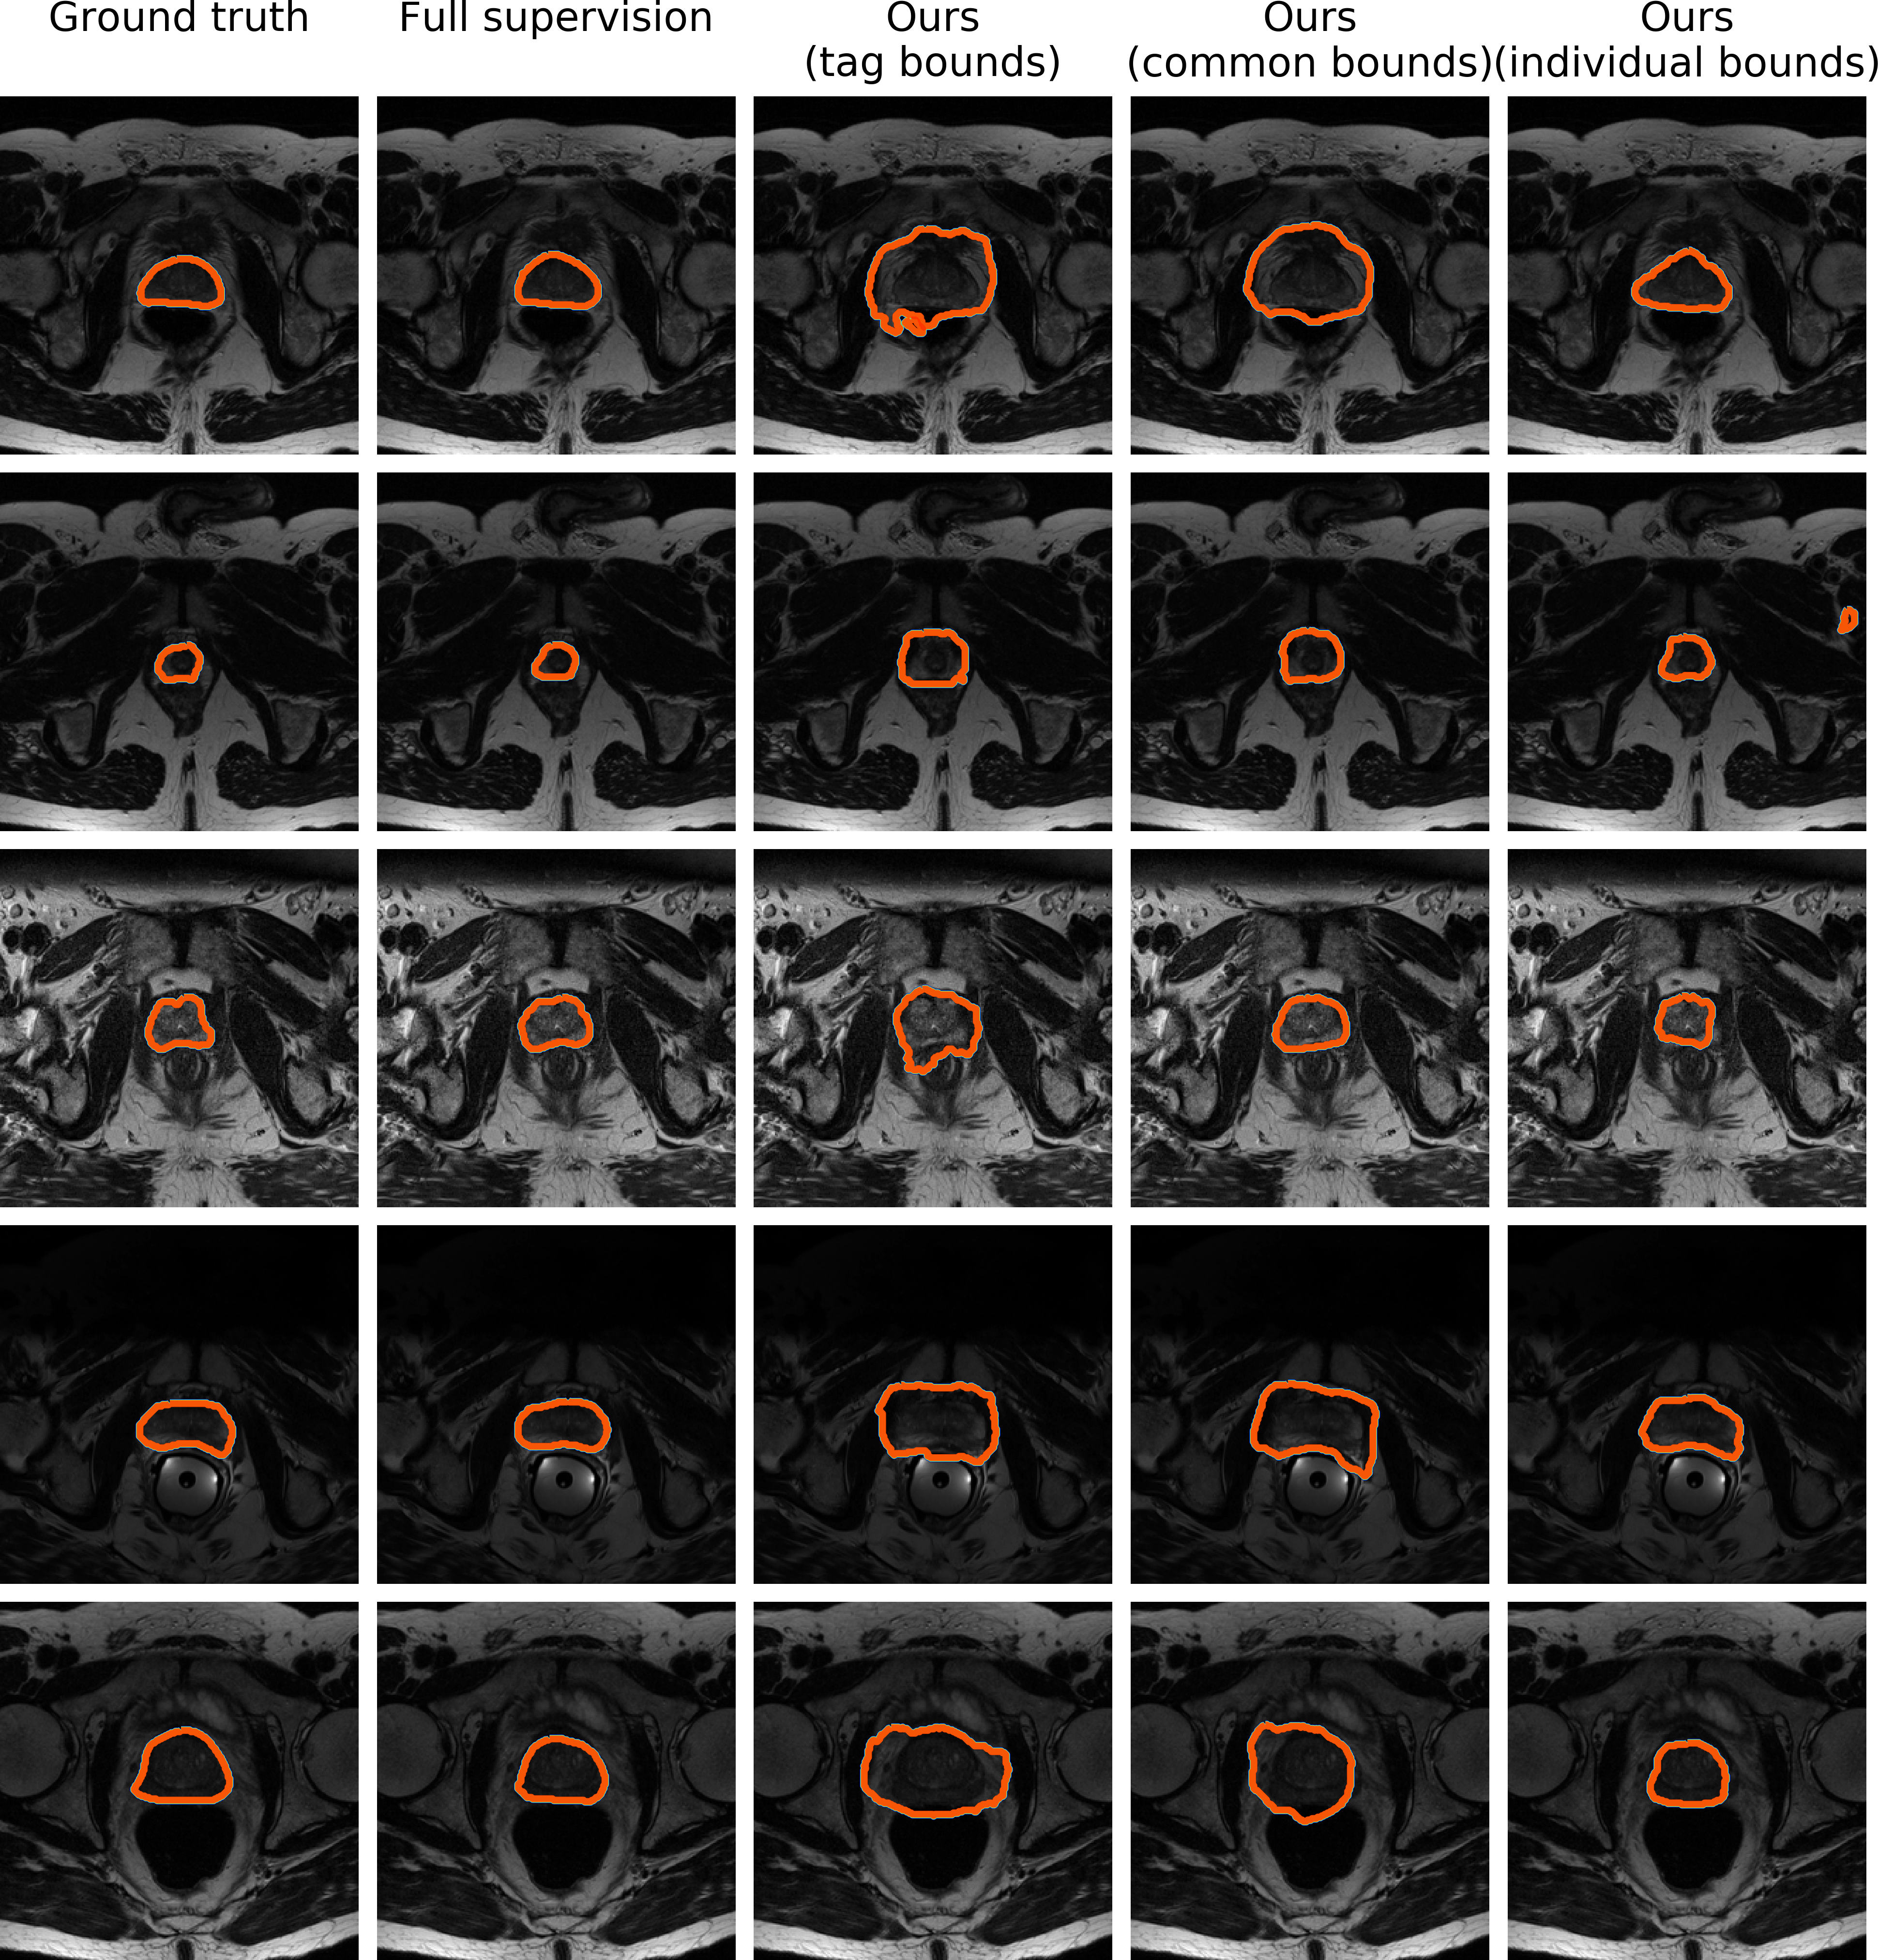

Prostate segmentation task

As in the previous case, we depict the results of full supervision, tag bounds, common bounds and individual bounds. Both the tags and common bounds locate the object in a similar fashion, but both have difficulties finding a precise contour, typically over-segmenting the target region. This is easily explained by the variability of the organ and the very low contrast on some images. As shown in the last column, using individual bounds greatly improves the results.

Refer to caption

Figure 7: Qualitative comparison of the different levels of supervision. Each row represents a 2D slice from different scans. (Best viewed in colors)